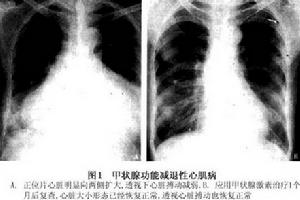

2.胸部X線片平片顯示心影普遍性擴大透視下可見心臟搏動遲鈍,幅度小(圖1)。

對比圖1.與冠心病鑑別甲減常以心血管系統異常表現突出,非專科醫師往往誤診為冠心病。下列幾點有助於鑑別: